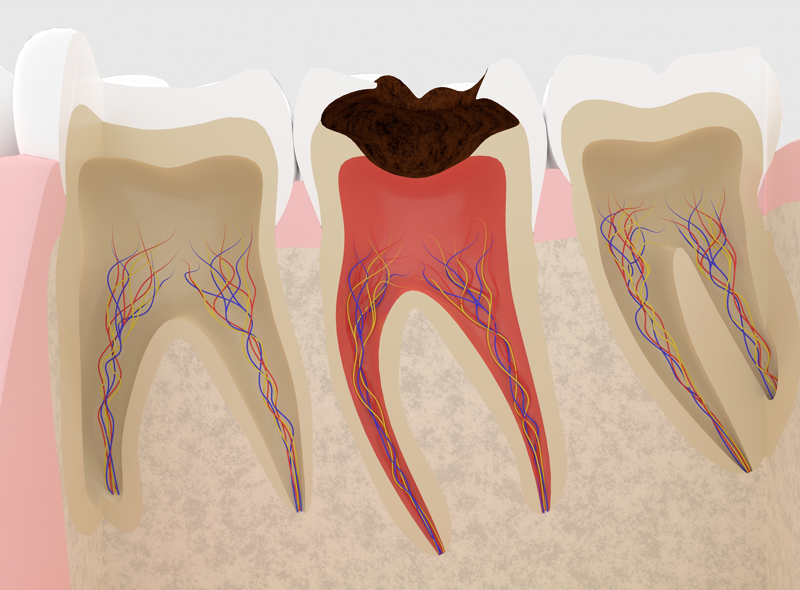

「根尖性歯周炎」になりやすくなる

根尖性歯周炎とは、歯の中の神経の入っている管(根管)内で細菌が繁殖してしまい、歯の根の先の部分に膿が溜まってしまう状態を言います。

歯の神経がある状態ですと、歯の神経の持つ免疫力により、侵入してきた細菌をやっつけたりブロックしたりすることができますが、神経がとられてしまった歯は細菌に対する抵抗力が失われてしまっているため、細菌感染を起こしやすくなっているのです。

むし歯(根尖性歯周炎)

虫歯の場合は、かなり進行しないと抜歯することにはなりません。

しかし、中等度以上に進行しなければ自覚症状が出にくいといわれています。初期では痛みなどの自覚症状が少ないため気付きにくいです。

進行すると冷たいものや甘いものを食べた時にしみるようになり、痛みが生じます。さらに進行すると神経まで虫歯が到達し、何もしていなくても激しく痛みます。

最終的には歯の大部分が溶けて神経が死んでしまうため、細菌の感染が根の先端まで進み、根の先に膿の袋ができ(根尖性歯周炎)、治りにくくなることがあります。場合によっては抜歯することになります。若年層の場合、歯周病よりも虫歯で歯を失うケースが多いです。 -